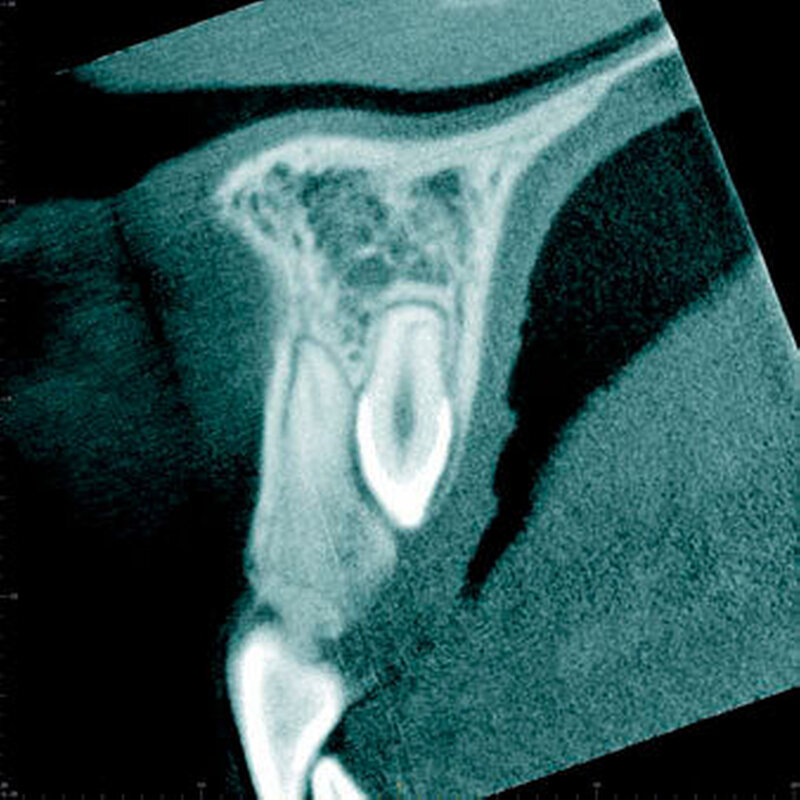

In einer aktuellen Arbeit berichteten Mossaz und Mitarbeiter (2014) über eine relativ hohe Prävalenz (22,8 Prozent) der Wurzel- resorptionen an benachbarten Zähnen, wobei besonders häufig überzählige Prämolaren zu Resorptionen führen (Abbildung 18). Für die Beurteilung der Wurzelresorptionen wurden digitale Volumentomografie (DVT) der Patienten herangezogen. In einer Studie aus China, welche ebenfalls DVT-Bilder beurteilte, wurde über eine deutlich geringere Häufigkeit von Wurzelresorptionen (1,6 Prozent) berichtet [Liu et al., 2007]. Im Gegensatz zu den Daten aus der Schweiz war Diagnose und Bewertung von Wurzelresorptionen kein primäres Ziel dieser Studie und es wurde auch keine Information über das Ausmaß der Resorptionen gegeben.

Daher könnte diese Studie leichte oder mäßige Wurzelresorptionen nicht eingeschlossen haben, was zumindest einen Teil des doch deutlichen Unterschieds in den Prozentsätzen erklären würde. Studien, welche Panoramaschichtaufnahmen zur Diagnose von Wurzelresorptionen heranziehen, berichten über Resorptionsraten zwischen 4,7 Prozent [Gündüz et al., 2008] und 7,6 Prozent [Hyun et al., 2009]. Tyrologou und Mitarbeiter (2005) berichteten sogar, dass keine Resorption im untersuchten Patientengut vorhanden waren. Allerdings wurden in dieser Studien nur Mesiodentes beurteilt, wo Wurzelresorption benachbarter Zähne eher selten vorkommen [Mossaz et al., 2014]. Generell lässt sich festhalten, dass zweidimensionale Röntgenaufnahmen für die Diagnose von Wurzelresorptionen eher ungenau sind und diese so in bis zu 50 Prozent der Fälle übersehen werden [Ericson Kurol, 1987, Heimisdottir et al., 2005; Botticelli et al., 2011; Alqerban et al., 2011a].